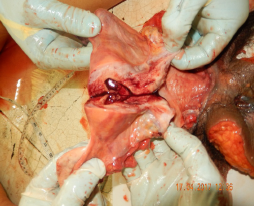

Canal vaginal. Se procede al corte longitudinal sagital por su pared anterior para visualizar estructura de tejido de la pared, así como la pared interna.

Región anal. Se visualiza periferia, se procede al corte longitudinal sagital a través de su pared posterior, pudiendo observar cara interna en sus estructuras adyacentes.

Figura 11 Corte longitudinal por la pared anterior de canal vaginal, cuello uterino, útero, visualizándose canal vaginal

Tras la detallada aplicación de la exenteración pélvica total, el examen interno de las estructuras pélvicas reveló la presencia de diversas lesiones consistentes con violencia sexual severa. Los hallazgos principales en el canal vaginal y su periferia se resumen en la Tabla 1, mientras que las lesiones identificadas en la región anal se detallan en el la Tabla 2. Adicionalmente, se documentaron visualmente las siguientes lesiones, ilustradas en las figuras 15 y 16, que acompañan este caso.

a nivel de esfínter anal externo y equimosis en cara interna de recto